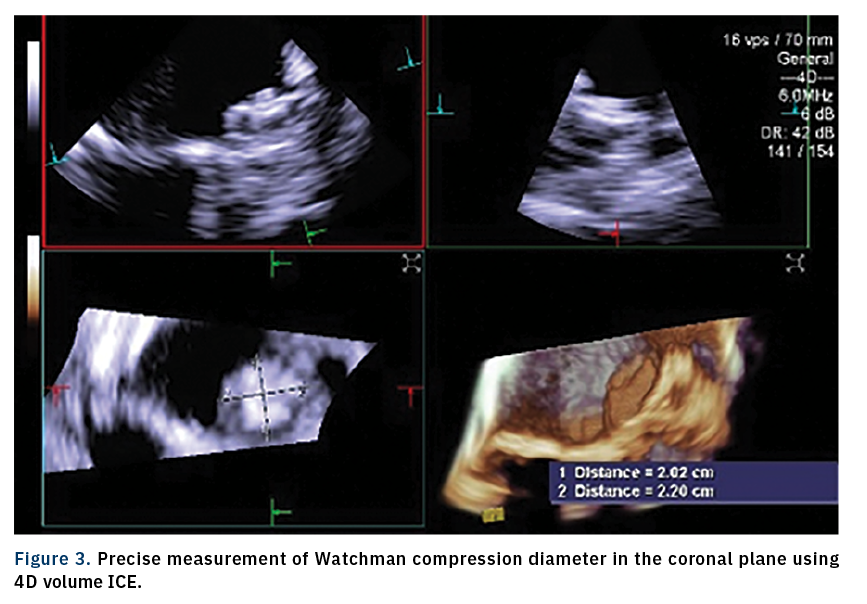

This case of left atrial appendage closure (LAAC) with a Watchman device (Boston Scientific) demonstrates the advantages of using 4D intracardiac echocardiography (ICE) over transesophageal echocardiography (TEE) and 2D ICE. An 87-year-old female with a history of paroxysmal atrial fibrillation was referred for LAAC. She received a contrast-enhanced preprocedural computed tomography (CT) scan to evaluate the LAA’s dimensions and anatomy. 4D ICE measurements (18.9 mm) of the LAA ostium correlated well with CT (18.2 mm). Since the patient could not tolerate long-term anticoagulation medication due to her condition, she underwent a Watchman procedure. Precise measurement of the landing zone predeployment and PASS (Position- Anchor-Size-Seal) criteria was performed using 4D ICE (ACUSON SC2000 PRIME ultrasound system, Siemens Healthineers). The Watchman device was deployed with the 4D ICE catheter positioned in the mid left atrial view displaying multiplanar reconstruction imaging, rather than with multiple views using 2D ICE. Device implantation occurred under conscious sedation and was free from complications; the patient was discharged the same day.